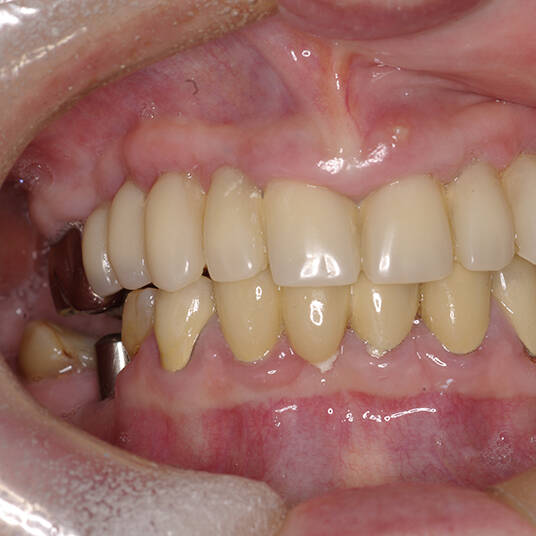

Na Clínica Pontes Odontologia, somos referência em implantes dentários em Fortaleza, oferecendo tratamentos de alta qualidade e tecnologia de ponta. Os implantes dentários são estruturas de titânio posicionadas cirurgicamente no osso maxilar ou mandibular para substituir as raízes dos dentes ausentes. Essa técnica permite a fixação de próteses personalizadas, restaurando a função mastigatória, a estética e a autoestima dos nossos pacientes.

Utilizamos a tecnologia CAD CAM, um sistema avançado que possibilita a confecção precisa das próteses dentárias diretamente sobre os implantes. Esse método inovador garante um ajuste perfeito, um resultado estético superior e proporciona muito mais conforto e durabilidade. Com o CAD CAM, nossos pacientes contam com um processo mais rápido e previsível para alcançar o sorriso desejado.